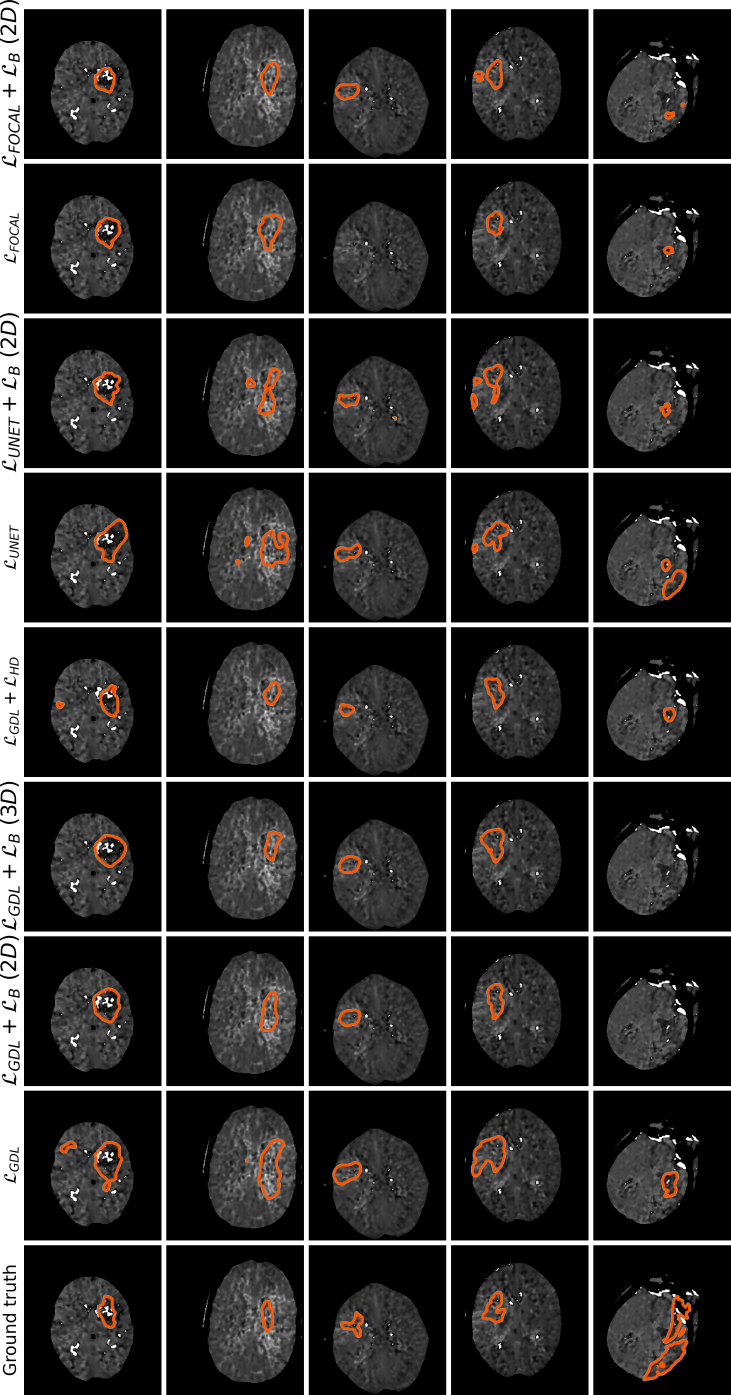

Qualitative evaluation

Qualitative results are depicted in Fig. 4. Inspecting these results visually, we can observe that there are two major types of improvements when employing the proposed boundary loss. First, as the methods based on DSC losses, such as GDL, do not use spatial information, prediction errors are treated equally. This means that the errors for pixels/voxels in an already detected object have the same importance as the errors produced in completely missed objects. On the contrary, as our boundary loss is based on the distance map from the ground-truth boundary , it will penalize much more such cases, helping to recover small and far regions. This effect is best illustrated in Fig. 1 and Fig. 4 (third row). False positives (first row in Fig. 4) will be far away from the closest foreground, getting a much higher penalty than with the GDL alone. This helps in reducing the number of false positives. Additional qualitative results for other base losses, and their combination with the proposed boundary loss, are depicted in Figures 5, 6. These figures also show failure cases (last column) of the boundary loss.